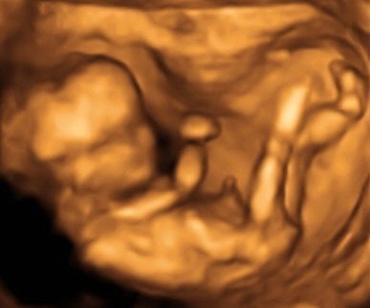

In cursul acestei saptamani, nivelul de dezvoltare cerebrala la care ajunge fatul permite acestuia sa simta durerea.

In cursul saptamaniilor 14 - 15 este foarte posibil sa percepi pentru prima data miscarile copilului tau. Unele femei percep miscarea copilului ca un tremur usor, delicat...